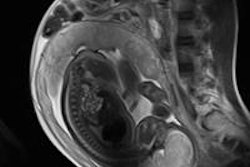

Fetal MRI is gaining clinical acceptance and being used more extensively across Europe, but there's still an urgent need to optimize and standardize patient care and imaging parameters to realize its potential, avoid unnecessary repeat examinations, and improve image quality and efficiency, according to a team of researchers from a top London facility.